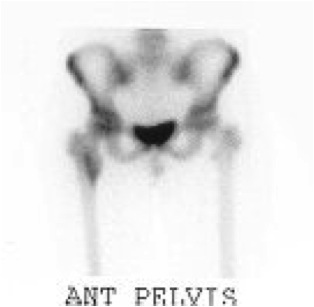

Bone Scan

Look fo occult bone metastases

Ewings proximal femur involving femoral head